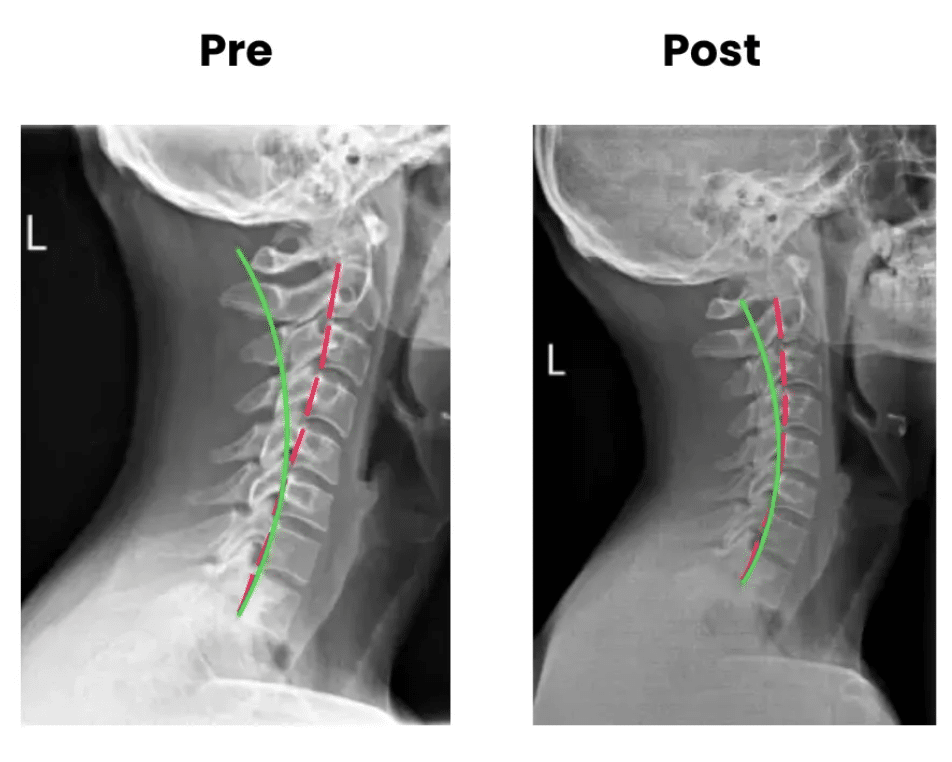

State-of-the-Art Technology – Latest FDA-cleared X-ray digital imaging and spinal decompression systems